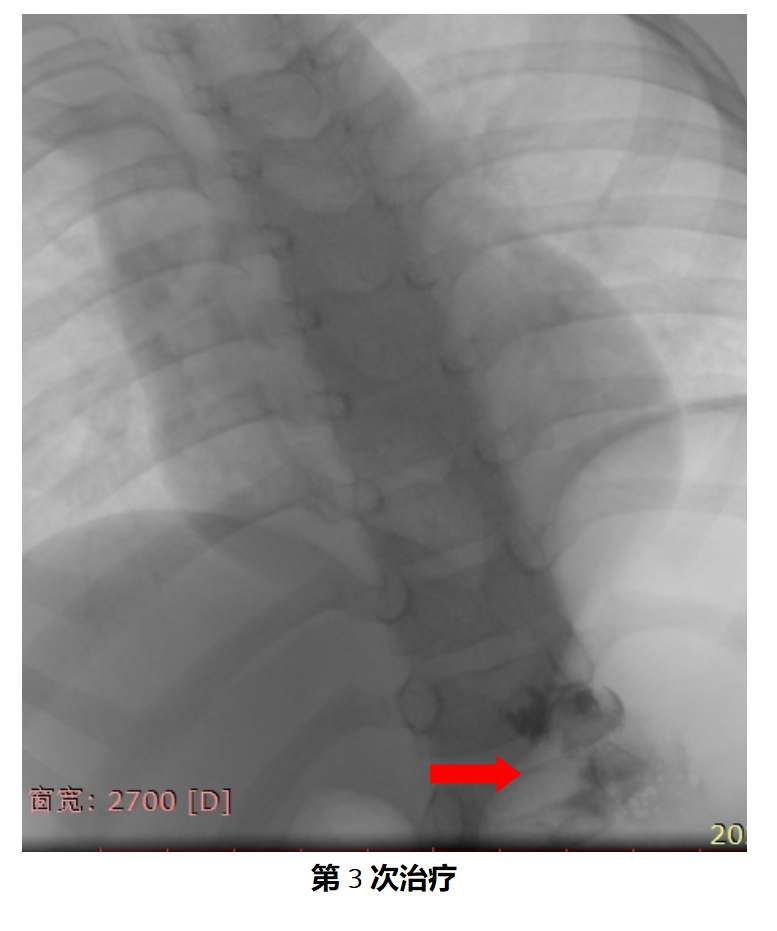

二、手术过程

在安排的手术时间,家长如约住院,顺利完成术前准备,手术当天,患儿在全麻的过程中完成了手术,手术仅耗时半小时,术中无出血,手术过程非常顺利,术后孩子也没有任何不适,身上也没有任何伤疤。共住院3天,患儿平稳出院。

三、术后恢复情况

接着,患儿又进行两次的介入治疗,肿物逐渐缩小,本患儿为巨大腹壁淋巴管瘤患儿,共介入治疗3次,患儿病灶基本完全恢复正常。微创、无痛、不遗留伤疤、花费小,推荐介入治疗为淋巴管瘤患儿的一线治疗方案。家长满意度高,我们也由衷地替患儿开心!

12. 什么是微创介入治疗?

淋巴管瘤影像引导经皮硬化(PSE)术主要是在超声及大型数字减影血管造影机 (DSA)引导下,用穿刺针精准穿刺病灶并抽尽液体,注射硬化剂,使瘤体在硬化剂的作用下逐渐消退。